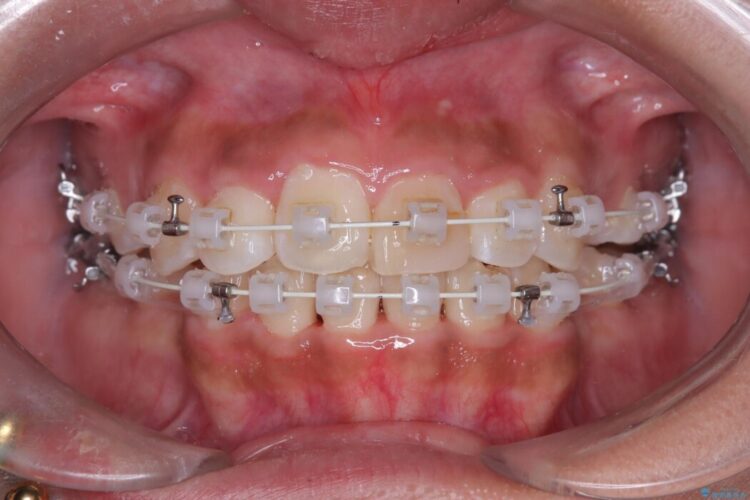

抜歯によって得たスペースを活用し、審美ワイヤーによる繊細な角度調整を行いながら前歯を後方へ移動。

突出していた口元のボリュームを段階的に抑制し、理想的なバランスへと導きました。

機能面では上下の緊密な咬合を確立し、審美面ではEラインの劇的な改善を実現しました。 形態と機能の両立により、患者様の満足度が非常に高い仕上がりとなりました。